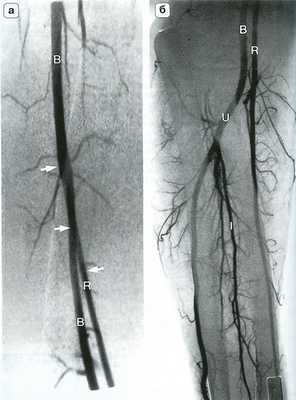

Рис. 14.4. Артериальная анатомия (а) и костные ориентиры (б) локтевого сустава. Плечевая артерия (В) делится на уровне локтевого сустава на лучевую (R) и локтевую (U) артерии. Межкостная артерия (I) является ветвью локтевой артерии, которая в некоторых случаях продолжается на кисть. RR - лучевая возвратная артерия; UR - локтевая возвратная артерия.

Рис. 14.6. Высокое отхождение лучевой артерии. На ангиограмме плеча (а) и предплечья (б) представлен вариант высокого отхождения плечевой артерии (R - стрелки) на уровне средней трети плеча. В - плечевая артерия; I - межкостная артерия; U - лучевая артерия